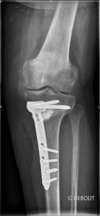

Arthrose interne du genou sur déformation du squelette en genu varum /

Traitement chirurgical côté gauche dans un premier temps par ré-axation grâce à une ostéotomie tibiale de valgisation